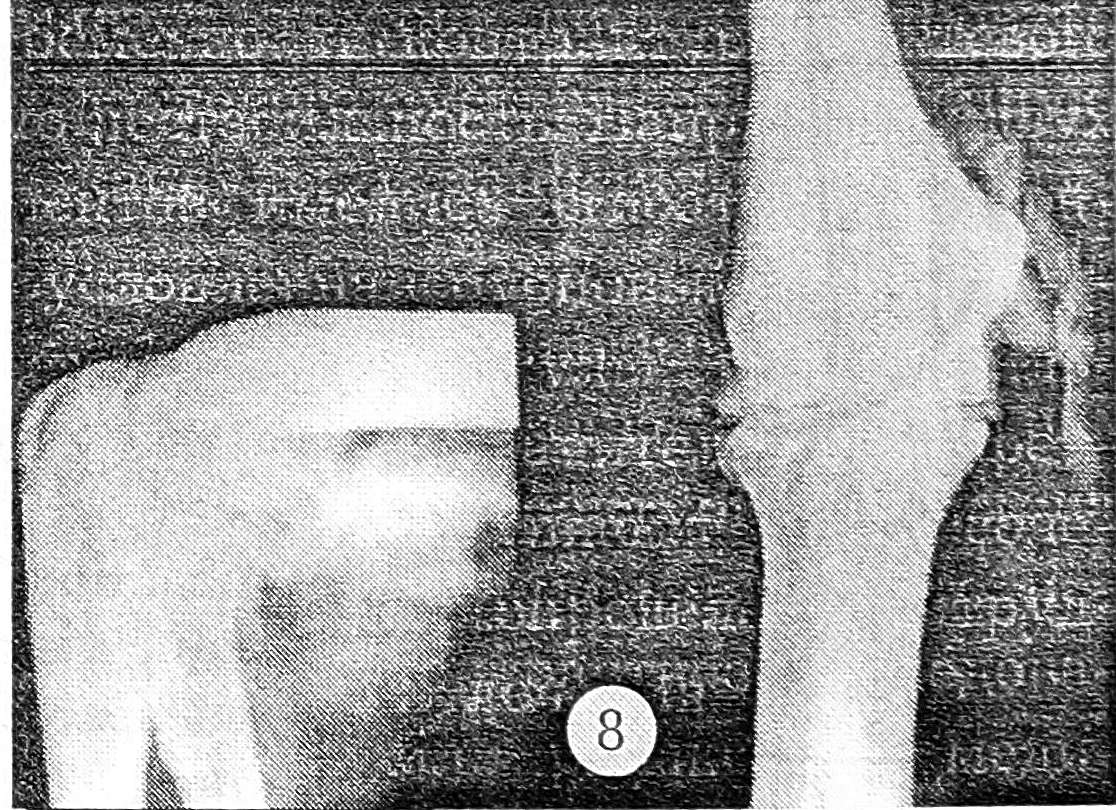

II | То же | Предплечье пассивно отводится на 10°, атрофия мышц плеча (2 см) и предплечья (1 см) | Ширина внутреннего отдела суставной щели в больном суставе в 2 раза больше, чем в здоровом (рис. 5) | Увеличение полости сустава или нарушение ее герметичности по внутренней поверхности сустава (рис. 6) | 19 |

Рис. 5. Рентгенограмма левого локтевого сустава, выполненная в специальной укладке: нестабильность II степени.